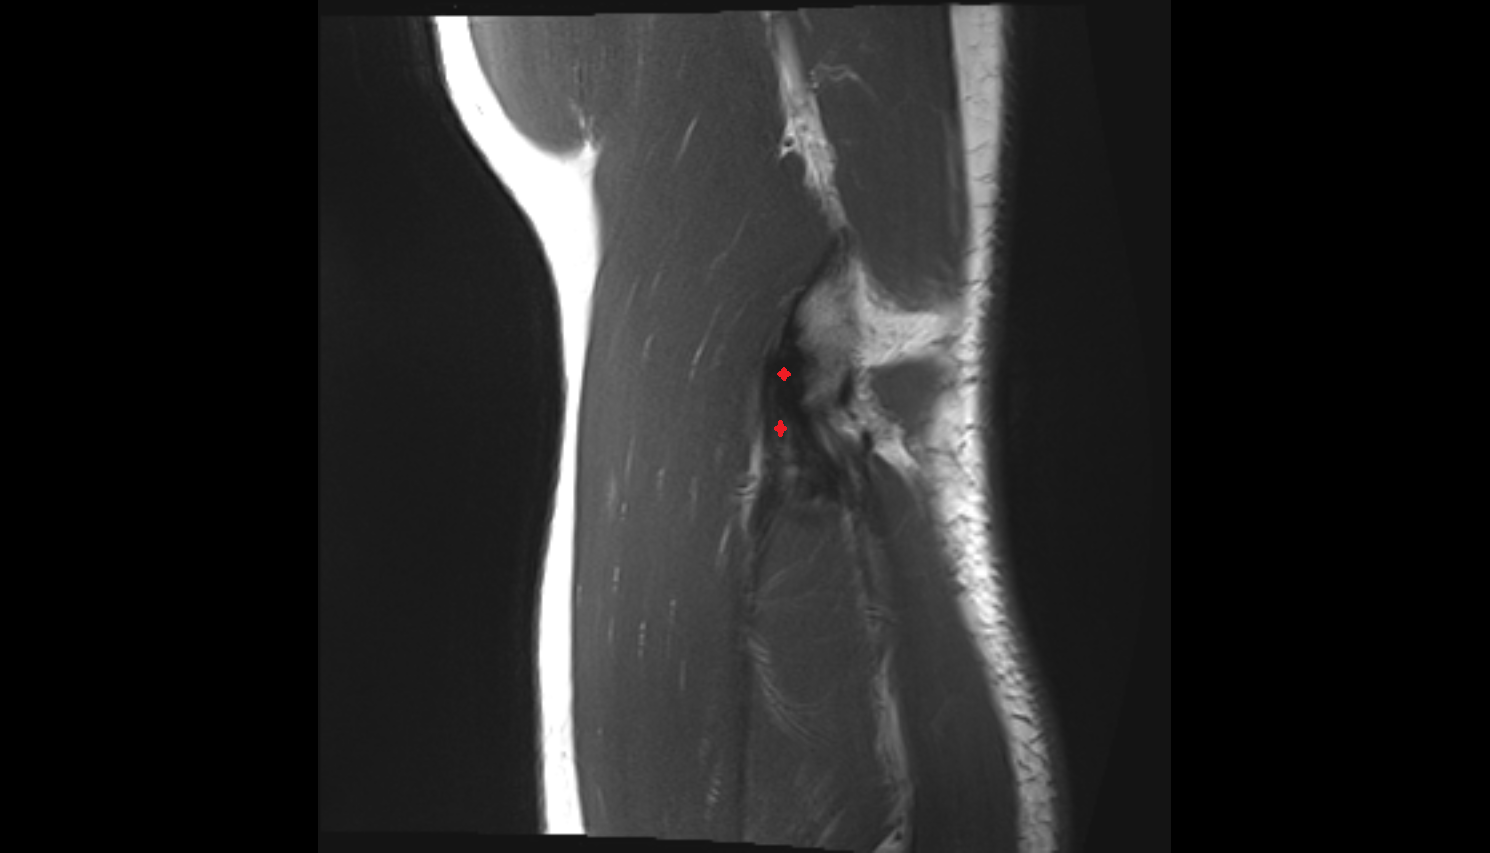

- Anterior cruciate ligament

- Posterior cruciate ligament

- Knee Joint